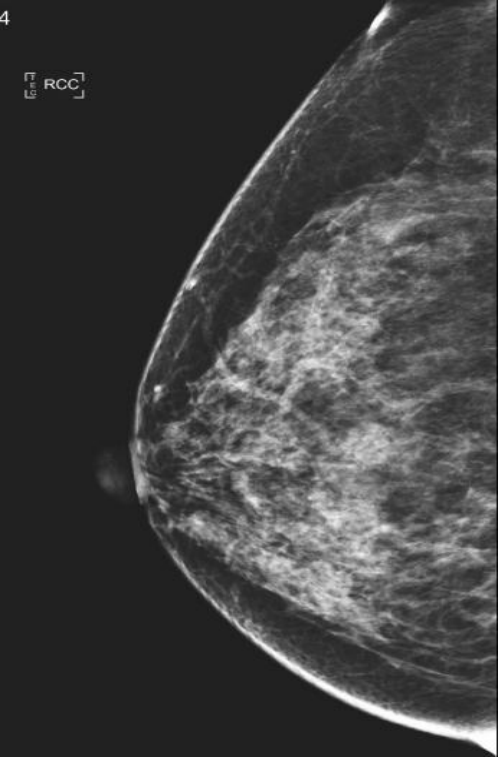

(3)非高危女性从40周岁开始,每年做一次乳腺钼靶筛查;对于有乳腺癌家族史者、未育、月经初潮早等高危因素的女性从35周岁开始,每年做一次乳腺钼靶筛查。而且,女性最好选择在经期结束3-7天进行乳腺钼靶检查。数字化乳腺钼靶是目前国际推荐的乳腺癌筛查手段。

乳腺X线检查是提高乳腺癌早期诊断的主要手段。全数字化平板乳腺机在早期临床诊断乳腺疾病中具有举足轻重的地位。